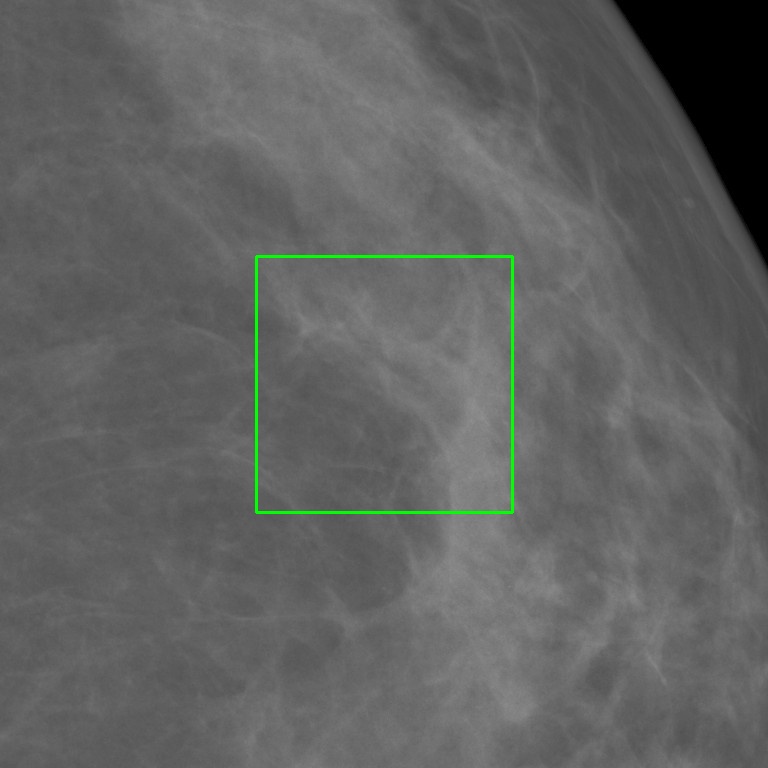

To overcome these challenges, this paper introduces MAMmography ensemBle mOdel (MAMBO), a novel approach that leverages an ensemble of diffusion models to generate mammography images at their native resolution. MAMBO uses a patch-based approach for generation which is conditioned both on local and global (full-image) context. In a nutshell, MAMBO involves the development of three distinct models: the first generates “standard”-resolution ( pixels) images to provide global context; the second increases the resolution to create local context for the target patch; and the third combines the outputs of both models to guide the generation of high-resolution patches, which are then reconstructed into a full-resolution synthetic mammogram. An example of a synthetic image generated by MAMBO is shown in Fig. 1. The image presents details at multiple resolutions, corresponding to the global and local contexts, and individual patch at full resolution. To the best of our knowledge, this is the first work to propose a diffusion model approach for generating very high-resolution synthetic mammograms.

This leads to a patch-based DDPM model based on the standard, three-channel U-Net architecture, within which the context information is provided at two scales (global and local) using the additional input channels, as shown in Fig. 2:

where represents the generated patch, and and represent the global and local context, respectively. This model can be readily used to create high-resolution mammograms that are visually indistinguishable from the original.

What MAMBO can achieve in terms of qualitative results is presented in Fig. 1 and Fig. 3(d). MAMBO is able to generate high-quality images that are visually indistinguishable from the originals, representing plausible mammogram data to layman eyes. Results are also validated with expert radiologists, with quantitative results shown in Sec. 4.2.

Fig. 3(d) illustrates what MAMBO can achieve in terms of whole mammogram generation. When using global and local context data extracted from an original image, the denoised image (Fig. 3(b)) is difficult to distinguish from the original (shown in Fig. 3(a)). When providing only the original global context and generating local context and target patches from noise, we still observe good results, as we show in Fig. 3(d).